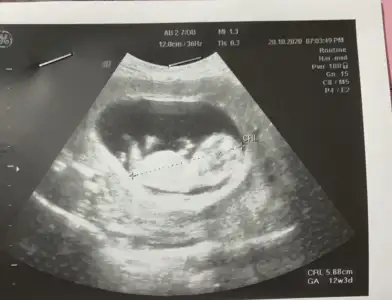

Merhaba Ikra meyra Ikra meyra canım, bir tahmin alabilir miyim ben de 13+2 olduk. :KK36:

Eklentiler

• 20201021_114201.webp

20201021_114201.webp

23,3 KB · Görüntüleme: 63

• 20201021_114209.webp

20201021_114209.webp

23,7 KB · Görüntüleme: 51

• 20201021_114216.webp

20201021_114216.webp

18,4 KB · Görüntüleme: 80

Cok Tesekkur ederim 🙏🏻🙏🏻doktor da göremedi, bir sonraki kontrolde inşallah görür anketi oylarım 🥰